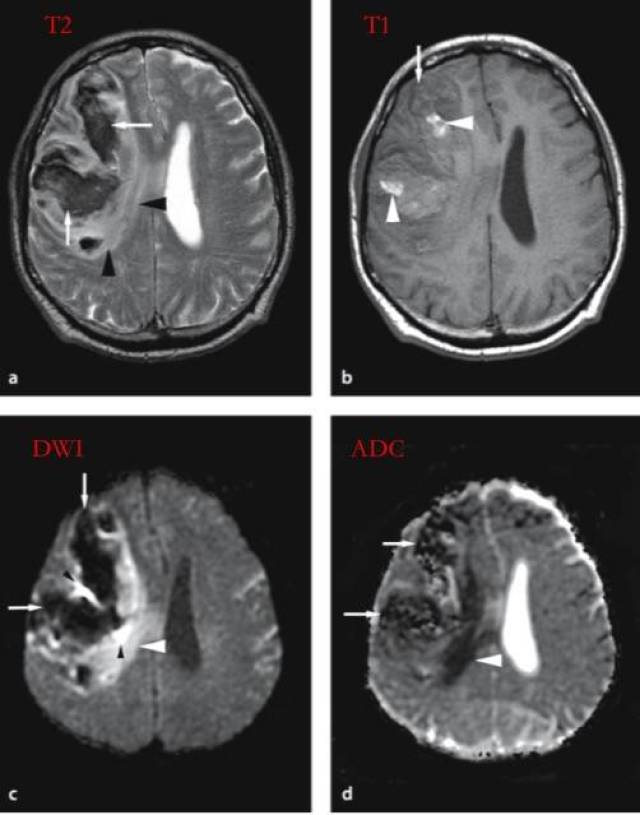

脑出血的核磁表现之dwiflair篇